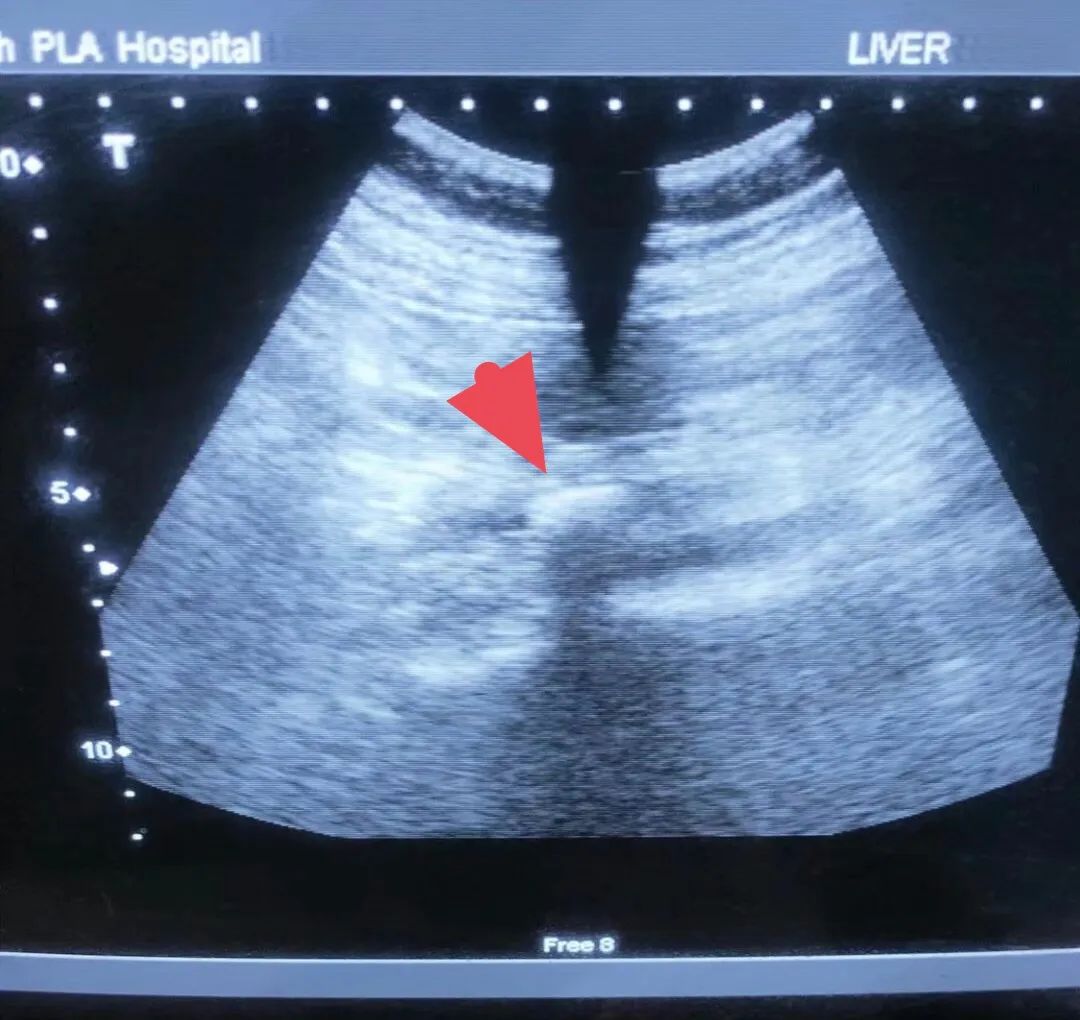

夏季炎热,气温升高,泌尿系结石的发病人数明显增多,近期泌尿外科收治的结石病人随之增加。小陈就是其中的一位,半夜突然左腰腹部疼痛难忍,他以为是普通的腹痛,想喝点热水,躺躺就好。可是半个小时过去了,疼痛更加剧烈,还伴有呕吐,血尿。受不了了,他马上打车到医院。经过急诊医师的初步检查,判断他可能是泌尿系结石梗阻了。经过CT检查,确诊左输尿管结石,收住泌尿外科进一步治疗。

一般可通过B超、腹部平片、CT、尿路造影、磁共振等检查发现。